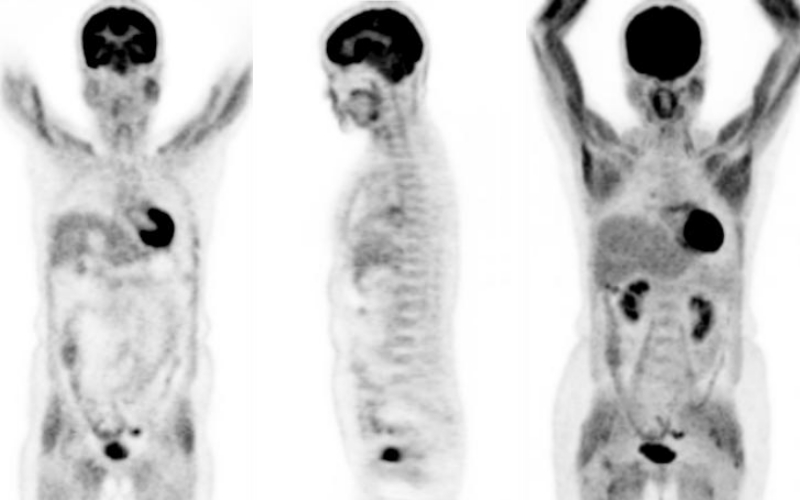

接下來就到了看圖說故事的時間,首先圖一就是高血糖的影像,患者的心肌、肝臟、骨骼肌與脂肪組織都十分的明顯,患者當時應該是偷偷吃了餐點沒講,所以才出現這樣的影像,2年後患者又回來檢查,這次很遵從指示有禁食,因此影像(圖二)就正常多了,因此呢選項(D)的敘述就錯了,FDG雖然會有一部份停留在血液中,但是後來還是會進入組織中,造成身體背景活性增加,而不是只單單停留在血管中。從這個道理去推想,(B)FDG被腫瘤處攝取的量會降低就相當合乎情理,因為腫瘤細胞攝取和利用葡萄糖的總量是固定的,如果血糖過高,FDG被攝取的比例就會降低,自然會造成腫瘤處的SUV值降低的情況,因此(C)剛好寫顛倒,至於SUV的定義請參考95年第1次高考第7題,至於(A)的選項,在高血糖的情況下,相較於圖一心肌、肝臟和肌肉組織的攝取增加,其實骨骼和淋巴的攝取量的增加相當不明顯,如果FDG真的會聚積在骨頭或者是淋巴結,其實就代表那裡真的是有問題,不會是高血糖所造成的,圖三左邊就是一位血糖高達300 mg/dL的患者(檢查前有注射胰島素),他的骨頭相較於右邊的正常FDG影像,可以發現骨頭的攝取非常的明顯,這是因為他的骨髓有造血方面的問題所致,這跟血糖高不高是不相干的。總結來說,正確的答案是(B)FDG被腫瘤處攝取的量會降低。

![]() |

| 圖一 |

| 圖二 |

| 圖三 |